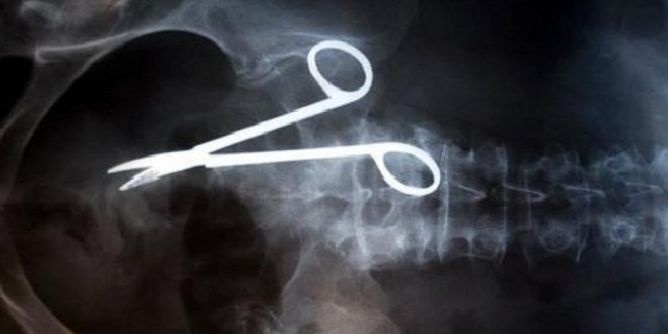

بعد 18 عاماً.. إخراج مقص جراحة من بطن رجل!!

في سابقة من نوعها، ظل مقص جراحي في بطن فيتنامي طيلة 18 عاماً دون أن يدري إلى أن استخرجه الأطباء في عملية جراحية.

ونقل التلفزيون الرسمي عن ما فان نهات (54 عاما) قوله إن الأطباء نسوا المقص على الأرجح في بطنه عام 1998 بعدما خضع لجراحة عاجلة بعد حادث سير.

وقال إنه كان يشعر بألم لفترة، ووصف له الاطباء دواء لقرحة المعدة إلا أن أشعة سينية أجريت له بنهاية العام الماضي أظهرت وجود مقص جراحي في معدته.

وقالت ترينه تي لونج مديرة مستشفى باك كان للتلفزيون إن المسؤولين يحاولون معرفة من الذي ترك المقص في بطن نهات.

وأضافت "حتى لو كانوا تقاعدوا سنبلغ عنهم.. هذا درس لجميع الأطباء".